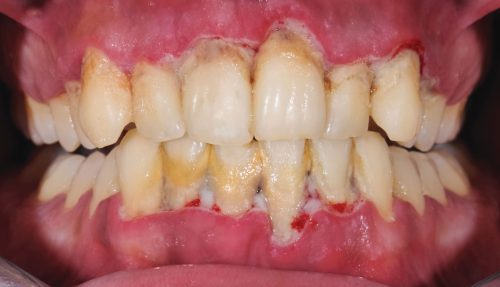

علائم عفونت لثه

عفونت دهان و لثه یکی از بیماریهای خاموش دهان و دندان محسوب میشود و دانستن اینکه چرا لثه عفونت میکند بسیار مهم است. که در بیشتر از 80% در مواقع بدون هیچ علامتی ظاهر میشود و تنها دندانپزشک پس از معاینه دقیق متوجه وجود آن خواهد شد. اما گاهی اوقات این عارضه همراه علائم خاصی پدیدار میشود که در حقیقت این علائم زنگ خطرهای این بیماری هستند و در صورت مشاهده هر کدام باید در سریعترین زمان ممکن برای پیشگیری از رشد عفونت و درمان به دندانپزشک متخصص مراجعه کنید.

- خونریزی لثه زمان نخ دندان کشیدن، مسواک زدن یا جویدن

- التهاب، افزایش حساست و متمایل شدن رنگ لثهها به قرمز پررنگ

- پسروی و عقب رفتن دندانها

- بوی بد دهان: بوی نامطبوع مداوم که با مسواک زدن رفع نمیشود، ممکن است نشانهای از عفونت باشد.

- احساس درد در ناحیه دندان و لثه، فک، سر و گوش

- احساس طعم ترشی یا تلخی در دهان

- لقی یا افتادن دندانهای دائمی

- به همریختن نظم دندانها

- ترشح چرک: در مراحل پیشرفته، ممکن است چرک بین دندانها و لثه دیده شود.